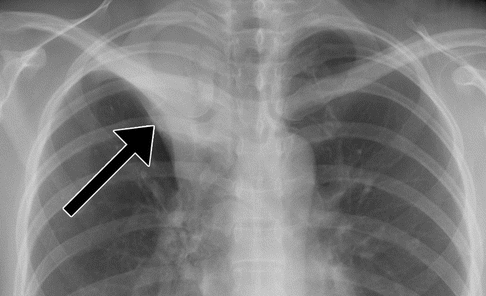

TB Primaire

- Adénopathies à centre hypodense (peut être l’unique trouvaille)

- Consolidations

- Epanchement pleural (d’hypersensibilité, sans BK dedans)